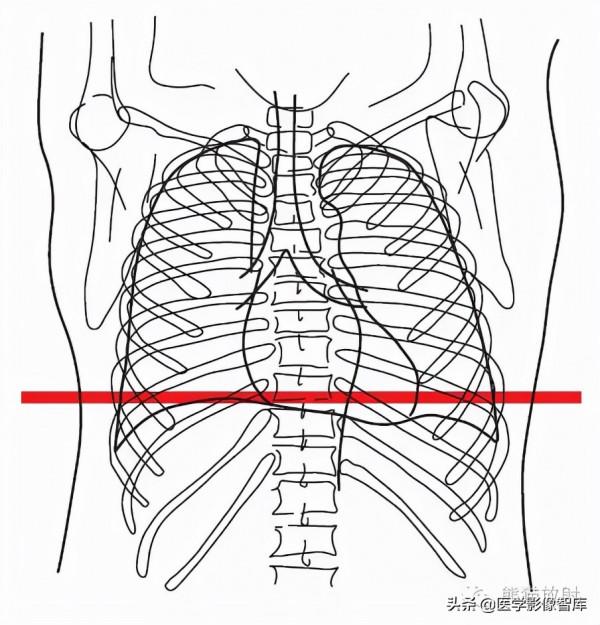

胸部

第五層:主動脈弓水平